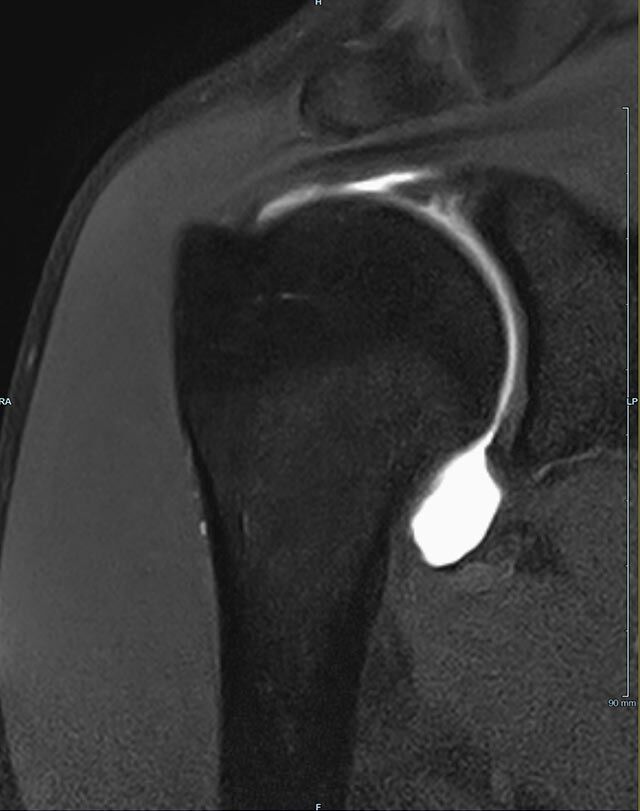

Gelenke

• Beurteilung von Knochen, Bändern und anderen Weichteilstrukturen der Gelenke nach Unfall.

• Arthrosediagnostik (Knorpelschaden)

• Impingement-Symptomatik

• Ursachenklärung bei wiederholter spontaner Gelenkluxation

• Ausbreitungsdiagnostik bei Gelenkentzündung, z.B. im Rahmen von rheumatischen Grunderkrankungen